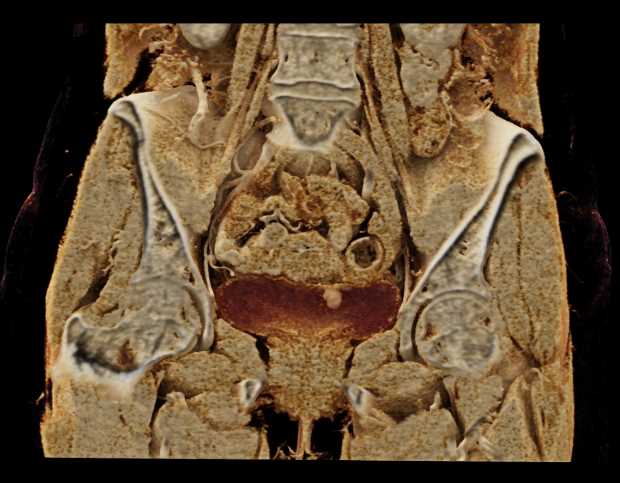

Bladder Cancer with Active Bleed